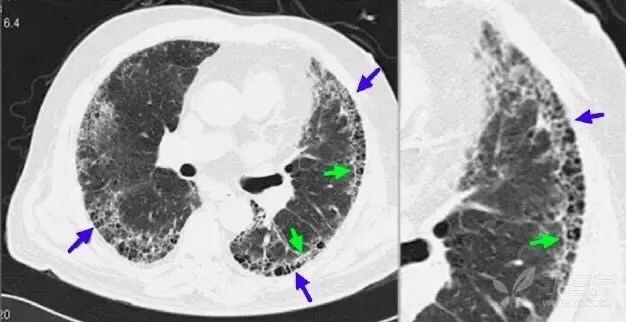

弥漫性特发性肺间质纤维化(IPF):表现为蜂窝样灶(蓝箭),并可见胸膜下线(绿箭)。IPF 平片示两肺纹理紊乱;CT 表现为双肺类网状、条索状灶,病变分布以胸膜下带较为显著。